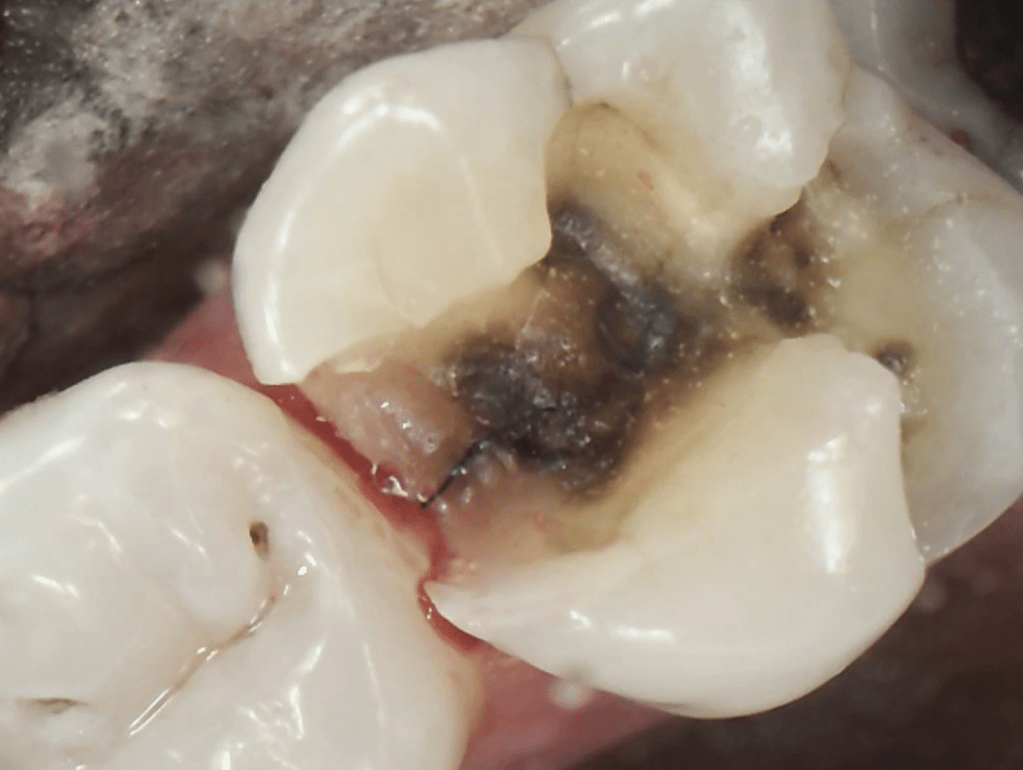

Broken Tooth with Cavity